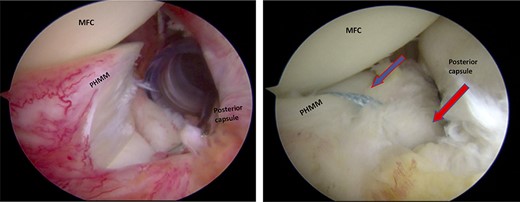

Trans-notch view of the posteromedial compartment of the left knee showing the blue arrow indicates the first lesion at the meniscosynovial junction of the red-red zone, and the red arrow indicates the second tear at the meniscocapsular attachment.

Standard diagnostic arthroscopy confirmed the presence of an intact ACL graft. Trans-notch arthroscopic visualization revealed a double meniscus ramp lesion (Figs 2–5). It was noted that the tear located at the meniscosynovial junction in the red-red zone of the PHMM was associated with MTL disruption, while the second tear was more posteriorly situated at the meniscocapsular junction and was associated with meniscocapsular attachment disruption. Probing of the meniscus resulted in its significant displacement.